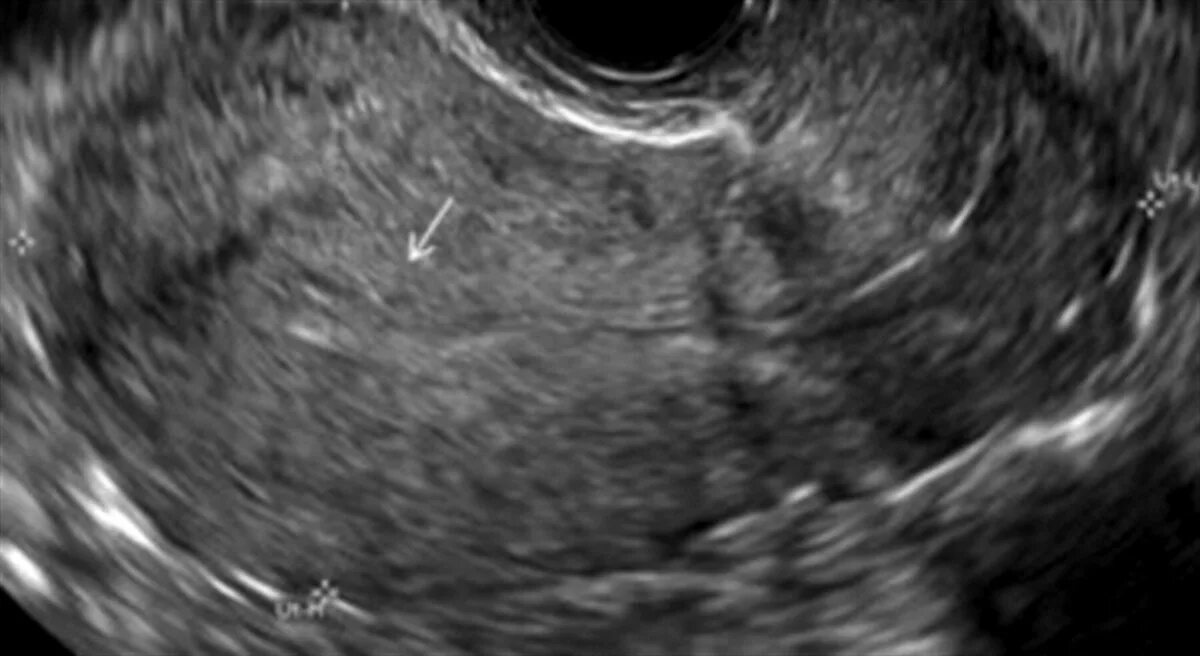

Диффузные изменения миометрия что это